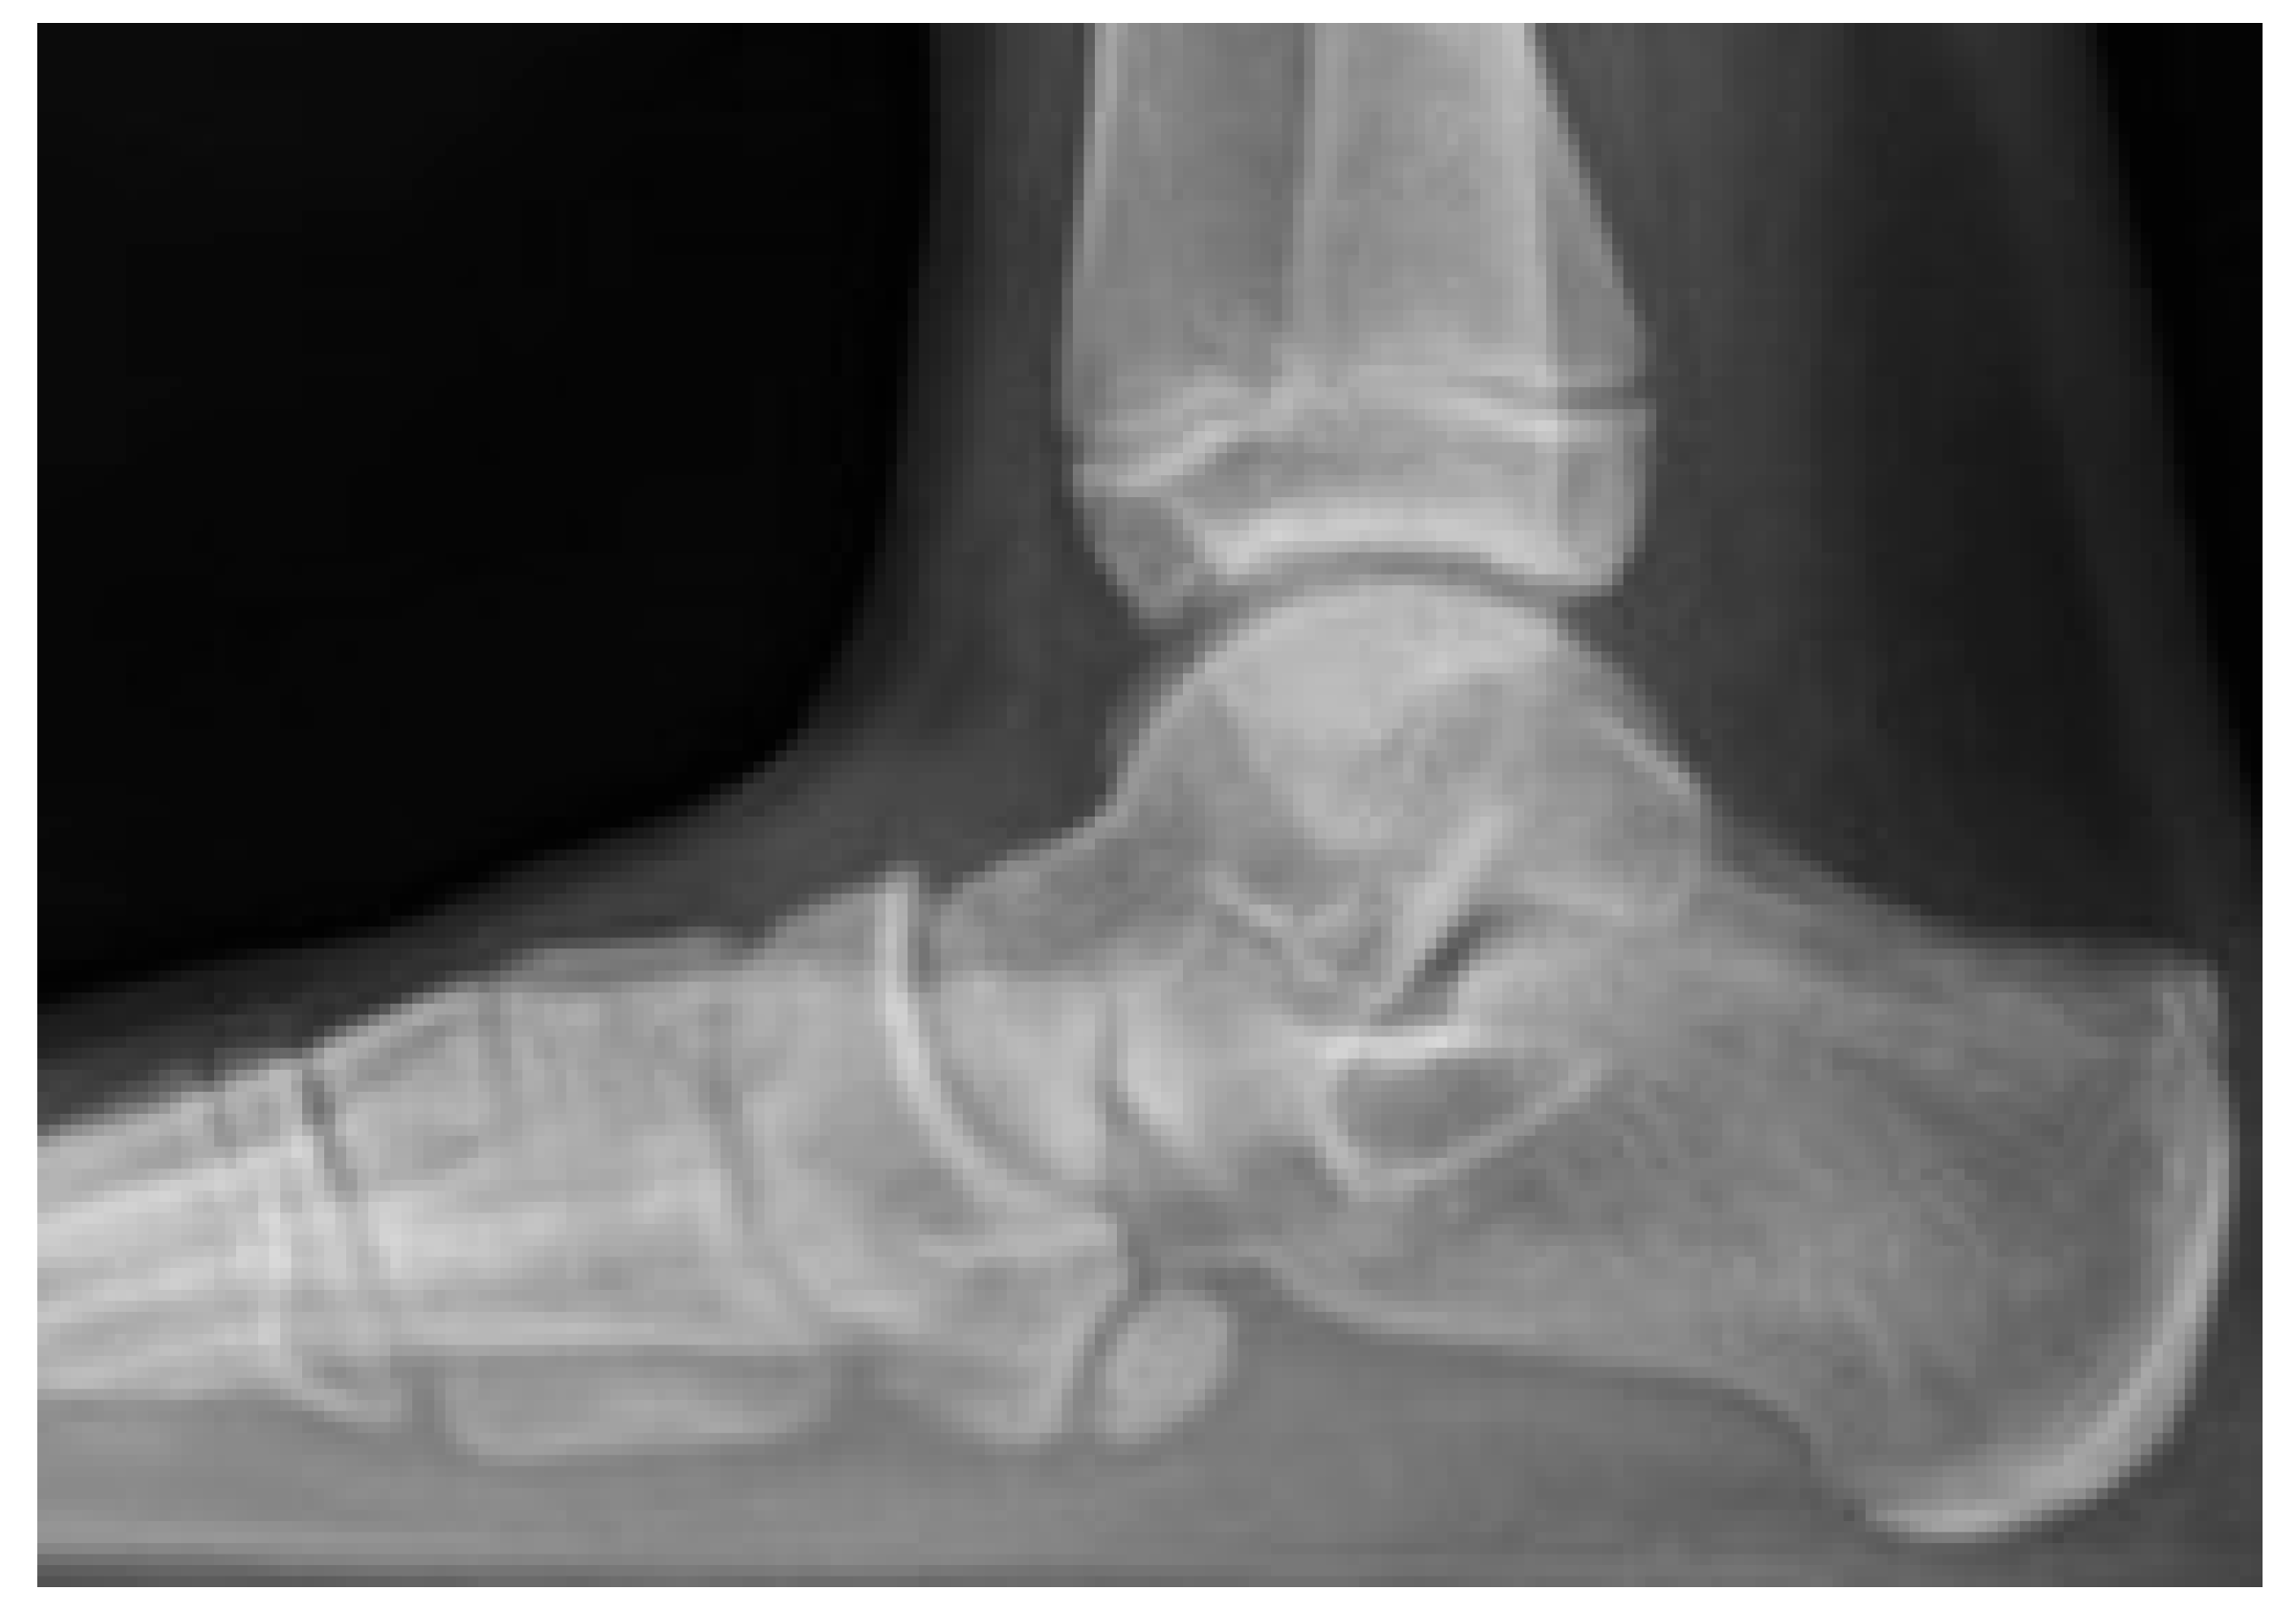

2.4.5. Diagnosis

Sometimes, navicular osteochondrosis can be an incidental finding on radiographs with no focal tenderness or pain. When pain is reported, the primary diagnostic tool is radiographic imaging. Regarding the role of radiographs in the study of navicular osteochondrosis, Mouchet and Roederer wrote, “The clinical presentation is almost negligible, radiography is everything.” [33]. Initial radiographs may show signs of bone sclerosis, which is indicative of altered bone metabolism and insufficient blood supply. The radiographic findings can range from subtle changes to more evident deformities, depending on the stage of the disease. In doubtful cases, it is helpful to perform a comparative radiograph of the contralateral healthy foot. Over time, radiographs may reveal a characteristic collapse and flattening of the navicular bone. In advanced forms, the navicular becomes very thin, exhibiting a biconcave or knife-blade appearance. The radiographic appearance of the navicular takes a long time to return to normal after healing, often requiring 1 to 2 years [14] (Figure 6).

Figure 6.

(Left): Radiograph of a 6-year-old male patient showing characteristic collapse and flattening of the navicular bone. (Right): Radiograph at 2-year follow-up after conservative treatment with non-weight-bearing casting, demonstrating good restoration of the navicular bone’s anatomical profile.